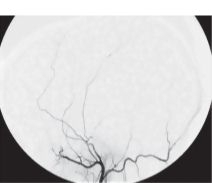

Digital Catheter Angiogram of the Left External Carotid Artery